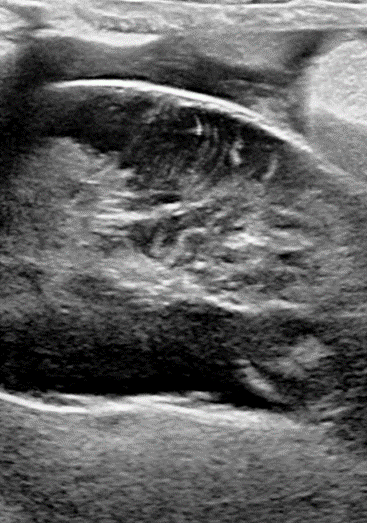

Abdominal ultrasound – this showed a distended gall bladder with organised stellate sediment filling the lumen. Free abdominal fluid was present and there was a local peritonitis surrounding the gall bladder. Otherwise within the abdomen there was some mild focal inflammation associated with the right limb of the pancreas and some diffuse hepatic change.